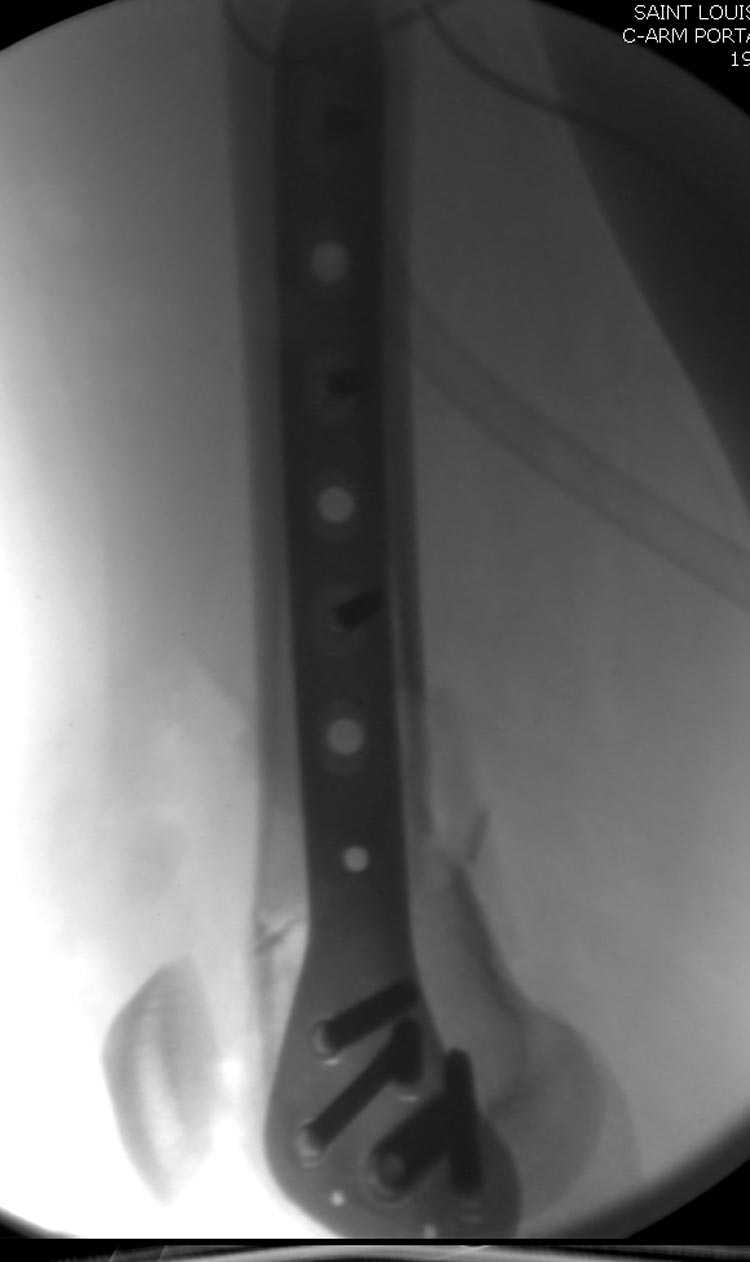

Почти все компании имеют пластины с угловой стабильностью, начиная от Stryker, Zimmer NCB и DePuy Polyaxial Plate . Если у NCB шуруп блокируется специальной шайбой, то Polyaxial Plate имеет вариабельный угол введения шурупов.

Поэтому такие меж и над- мыщелковые переломы более предпочтительным считается фиксировать мыщелковыми пластинами

Устанавливается из малого разреза "не вскрывая сустав" со стороны латерального мыщелка, и Insertion Jig позволяет установить пластину "мостовидно" перкутанно в проксимальном отделе, "не вскрывая и не трогая" место перелома.